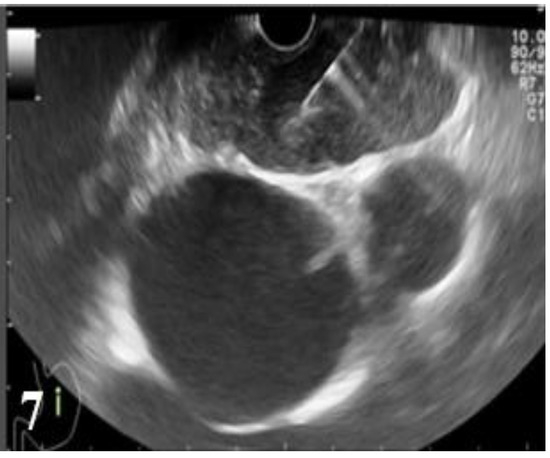

Figure 4.

EUS image showing a round lymph node with preserved hilum, with a diameter under 10 mm, located in the hepatic hilum.